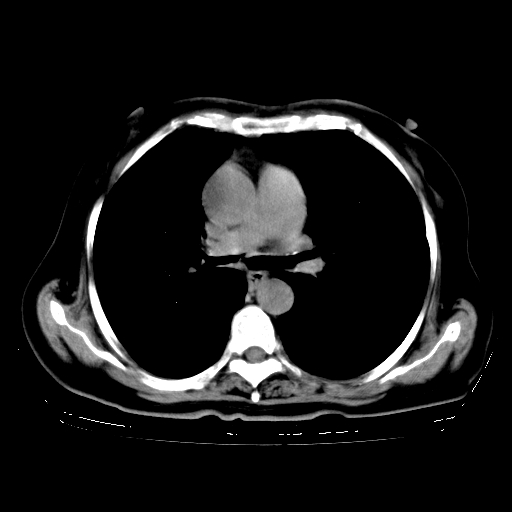

女,70岁,咳嗽、咳痰一个月,低热一周。

继发型肺结核,右下肺支气管内膜结核.右侧少量胸腔积液.主动脉夹层.

支气管内膜结核肺内播散.右侧少量胸腔积液.主动脉夹层.